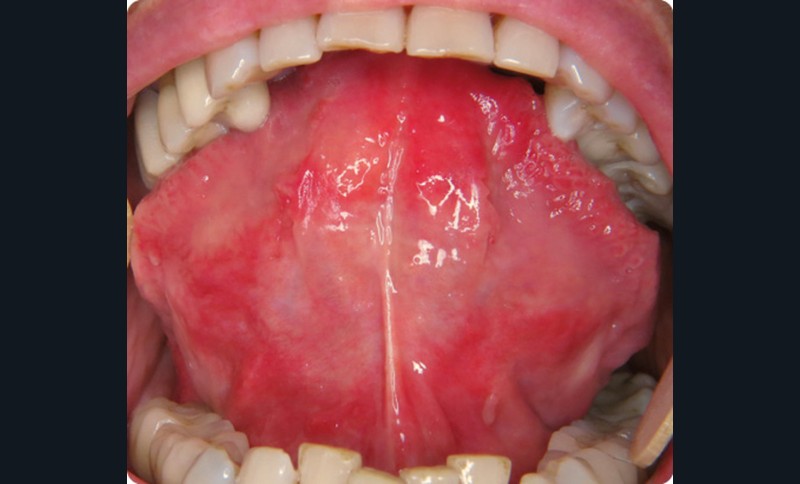

- L’examen endo-buccal révélait des plages érythémateuses de la face ventrale de la langue avec quelques ulcérations aphtoïdes millimétriques.

Une biopsie a été réalisée. Elle a mis en évidence un épithélium malpighien atrophique avec de nombreuses ectasies vasculaires dans le chorion.